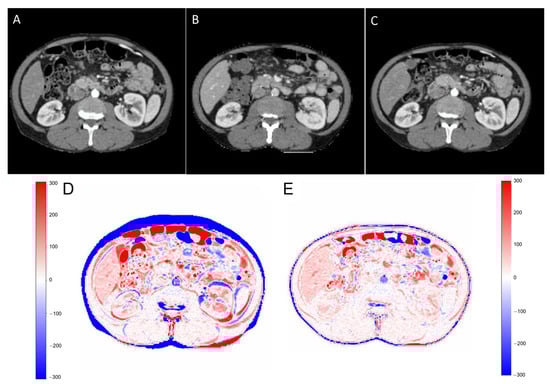

2.1. Data Preparation

2.3. Training and Testing of the Model

2.5. Evaluation Metrics